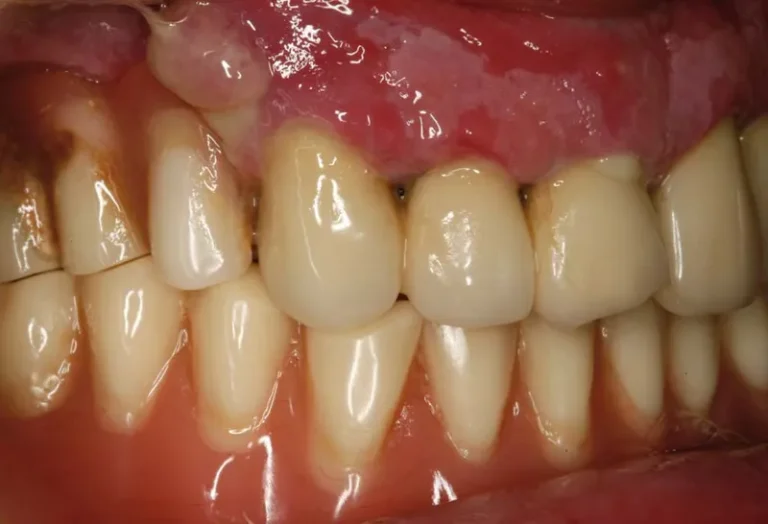

Si notas que tu implante dental se ha aflojado, es fundamental actuar con rapidez y contactar inmediatamente con tu dentista. Este problema puede deberse a diversos factores como infecciones, sobrecarga oclusal o pérdida ósea, y requiere atención profesional urgente para evitar complicaciones mayores. Mientras esperas tu cita, evita manipular el implante, mantén una higiene meticulosa…

La regeneración ósea es un procedimiento quirúrgico fundamental en implantología dental que permite recuperar el volumen y la densidad del hueso maxilar o mandibular cuando este se ha perdido. Este tratamiento se vuelve necesario cuando el paciente no dispone de suficiente tejido óseo para sostener un implante dental de manera segura y estable. Mediante el…